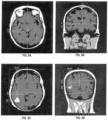

- FIG. 9A, FIG. 9B, FIG. 9C, and FIG. 9D show example MRI data showing scans of the head of a patient.

- FIG. 9A shows an axial T1 sequence slice containing the most apical image, including orbits used to measure head size.

- FIG. 9B shows a coronal T1 sequence slice selecting image at the level of ear canal used to measure head size.

- FIG. 9C shows a postcontrast T1 axial image shows maximal enhancing tumor diameter used to measure tumor location.

- FIG. 9D shows a postcontrast T1 coronal image shows maximal enhancing tumor diameter used to measure tumor location.